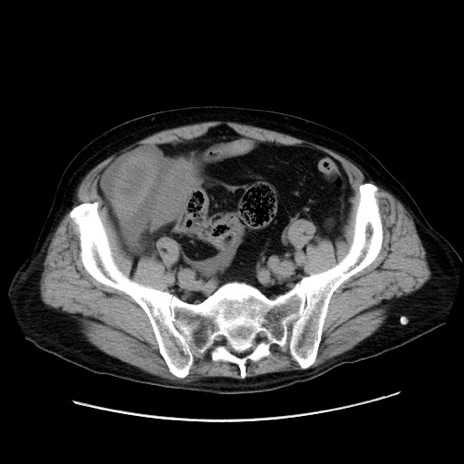

冠状断像

【症例】80歳代男性

【主訴】臍周囲痛

【現病歴】約6時間前から臍下部痛が出現。次第に腹部膨隆・背部痛も生じてきたため来院。背部痛の場所は変化しない。

【身体所見】意識清明、BT 36.3℃、BP  131/87mmHg、P 87bpm、SpO2 100%(RA)、臍周囲自発痛・圧痛あり、反跳痛なし、自発痛部位に一致して板状硬あり、腹部膨隆、腸雑音減弱、CVA tenderness両側陰性。

【データ】WBC 19600、CRP 0.33